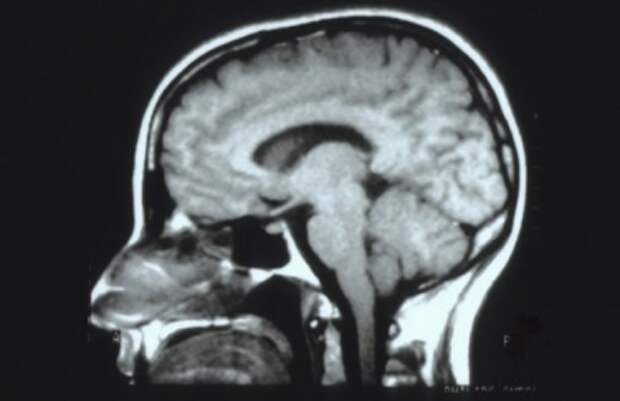

Ученые выяснили отличие мужского мозга от женского

Добровольцы прошли три теста: на запоминание, математическое мышление и вербальное общение.